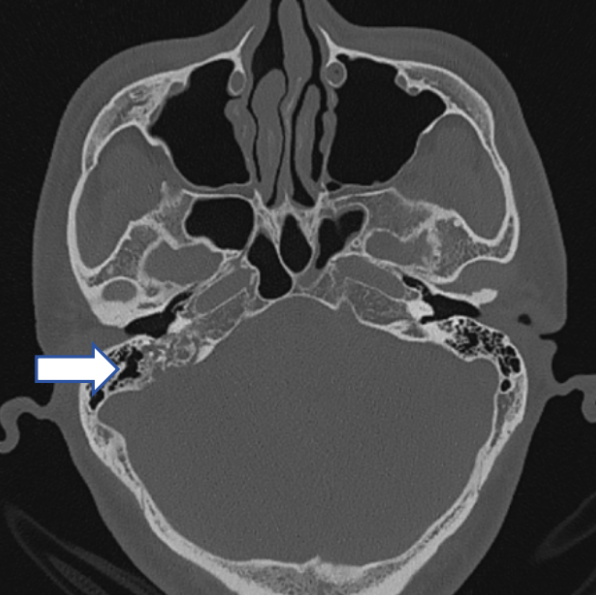

41岁的王先生,右耳耳鸣三月余,安静时明显,持续加重,有节律性,与脉搏节律一致,休息不好容易加重。查看双侧外耳道通畅,鼓膜稍浑浊。

CT发现右侧颞骨异常密度灶伴骨质破坏影,右侧内听道稍增宽。

图片

初步诊断

颞骨、颈静脉孔区占位